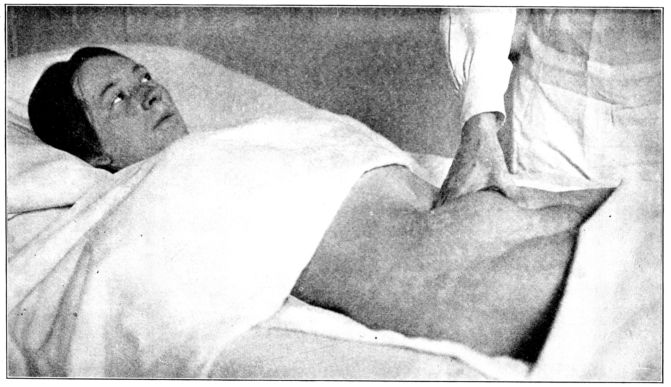

| 101. | Massaging fundus through abdominal wall | 282 |